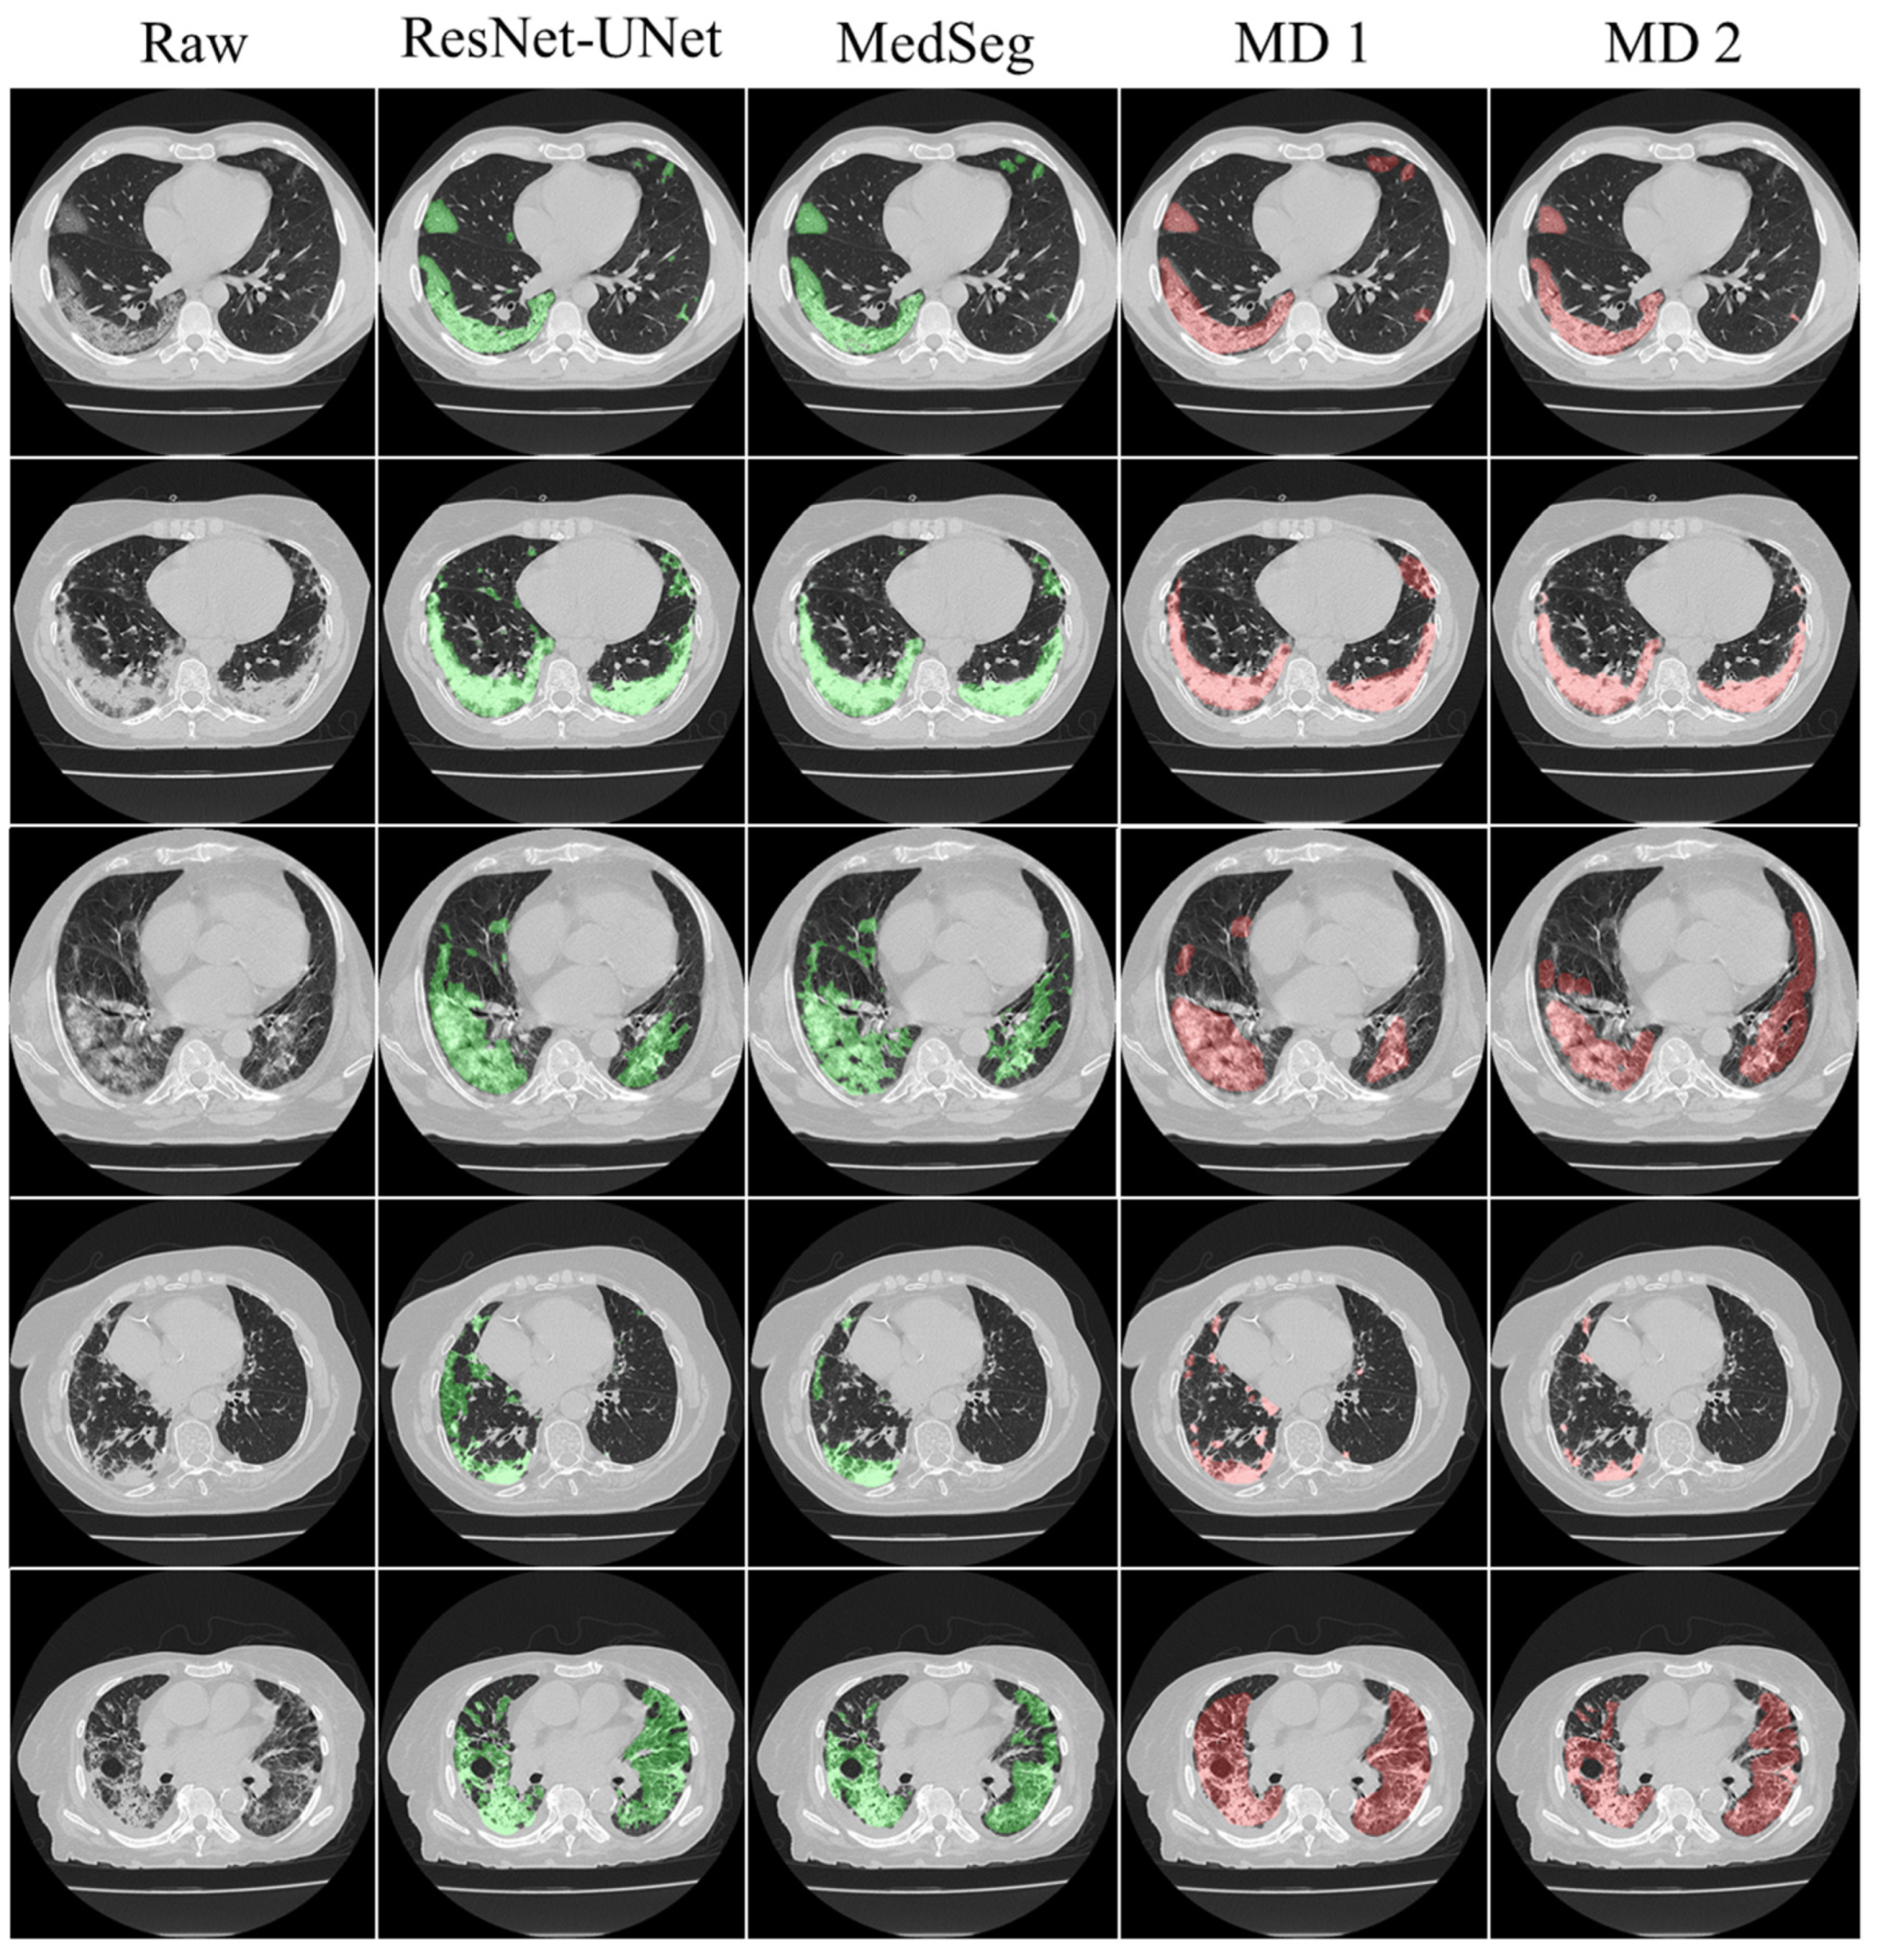

3.1. Results